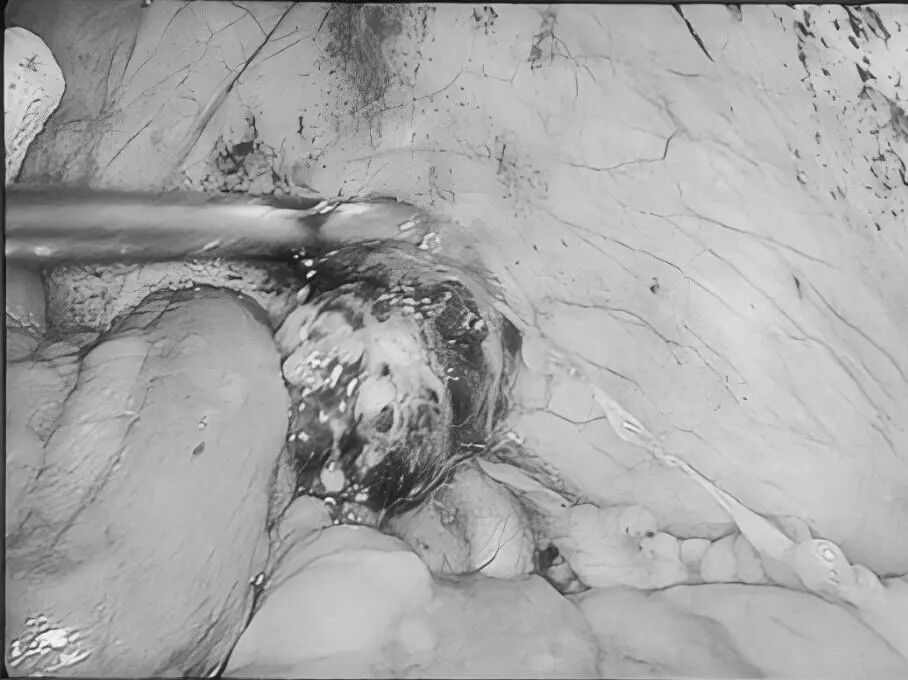

诊室里,经常能看到这样的画面:家长抱着哭得小脸通红、怎么哄都停不下来的宝宝,急急忙忙冲进来,“医生!快看看!孩子大腿根这里突然鼓了个包,越来越大!这可怎么办啊?!”——这种让人揪心的紧急情况,很多都是“小儿疝气”(俗称“小肠气”)惹的祸! 什么是小儿疝气? 简单说,就是宝宝肚子上有个“小洞洞”没长好(发病率为1%-4%),医学名称叫“腹股沟疝”,是小宝宝(尤其是男宝)很常见的一种情况。 为啥会这样?宝宝在妈妈肚子里时(先天性),腹股沟那里有个通道(学名叫“鞘状突”)本该自己关上的,但没关严实,就成了个“小洞洞”。当宝宝使劲哭闹、咳嗽、或者用力便便时,肚子里压力一大,一小段肠子或者组织就可能从这个“小洞洞”钻出,鼓起一个“包”。 最典型的表现:宝宝大腿根附近,出现一个“鼓包”,而且这个包在宝宝安静或躺平时,常常能自己缩回去(或者家长轻轻一推就能推回去)。 家长最关心的问题 1.必须要做手术吗? 在1岁以内有长好的可能,可以观察看看。超过1岁还没好,或者包块反复卡住(嵌顿)引起剧痛,千万别等了,尽早做手术,最佳手术年龄通常是1到3岁。 2.麻醉会不会伤脑子? 手术用的是全身麻醉,目前全球尚无研究证实规范全麻操作会影响智力或记忆力。宝宝就像睡了一个很沉很沉的觉,手术过程中完全没感觉、也不会记得。 为什么腹腔镜修补术比较适合宝宝? 传统开刀手术需在大腿根附近切开一个3厘米左右长的口子,手术后会留下挺明显的疤,恢复也慢。 腹腔镜修补术是通过肚子上3-5毫米(米粒般的大小)的小孔进行手术,同时能探查并处理对侧“隐性疝”,一次手术就搞定,不用再挨第二刀。术后一般6-8小时可以下床,24小时后能出院。 术前术后,家长这样配合更安心 术前准备 1.手术前6到8个小时别让孩子吃东西、喝水,防止打麻药时吐出来呛到。 2.按医生要求做抽血、凝血这些检查,看看孩子身体适不适合手术。 3.手术前一天给孩子洗个澡,把肚脐和大腿根附近洗干净。 4.多哄哄孩子,别让他哭得太厉害(哭狠了肚子里压力大,对手术不好)。 术后护理 饮食:术后6小时可少量喂水,无呕吐可逐渐恢复正常饮食。 活动:术后一周避免剧烈跑跳、哭闹或用力排便,防止腹压过高。 伤口护理:保持伤口清洁干燥,若发现红肿、渗液等不适,及时联系医生。 注:部分图片来源于网络,如有侵权,请联系删除。 贵州航天医院普外科专家简介 高大勇 普外科(肛肠外科)学科带头人、名誉主任,主任医师、教授 临床擅长:对中西医结合诊治肛肠学科各种常见病、多发病及疑难杂症等具有丰富的临床经验。 原遵义市第一人民医院(遵义医科大学第三附属医院)、遵义市中医院肛肠科主任。中华中医药学会肛肠分会常委,全国中医肛肠学科名专家,中国健康促进与教育协会肛肠分会常委,中国康复医学会肛肠疾病康复专业委员会常委,中国民间中医医药研究开发协会肛肠分会副秘书长,中国医师协会中西医结合肛肠医师专业委员会常委,国家二级心理咨询师,贵州省第一批中医名医工作指导老师,遵义市名中医,遵义市肛肠学会会长,遵义市肛肠质控中心名誉主任,遵义市中西医结合学会名誉会长,遵义市健康科普专家,原贵州省中西医结合学会肛肠分会副主任委员、贵州省中医肛肠质控中心副主任、遵义市医学会医疗鉴定委员会专家、遵义市卫生系列高评委。发表论文30余篇,主编和参编医学著作5本,主持省级科研课题2项、市级科研课题2项、院级科研课题1项。 梁 跃 中共党员,普外科党支部书记、主任,主任医师 临床擅长:对普外科各类肿瘤手术具有丰富的临床经验。 毕业于遵义医学院,遵义市医学会小儿外科学分会常务委员,遵义市肛肠协会理事,遵义市医学会核医学分会(第二届)委员会委员;荣获第三期“黔医人才计划”优秀学员称号;主持市级课题1项,完成省级课题1项,在国内各类刊物上发表论文10余篇。 钱科洪 民盟盟员,普外科副主任医师 临床擅长:从事普外科临床工作30余年,对各类普外科疾病的诊治、乳腺、甲状腺、胃十二指肠、结直肠等疾病及疑难杂症具有丰富的临床经验。 毕业于遵义医学院临床医疗系,2009年前往中山大学附属第一医院微创外科进修学习,在国内各专业期刊发表论文数篇。 贵州航天医院普外科简介 基本情况 贵州航天医院普外科成立于1968年,前身属于航天部O61基地3417医院外一科,1998年3417医院、3427医院合并后更名为普外科,下设胃肠外科、肛肠外科2个亚专业科室,拥有在全市较为先进的专科设备和技术,是中国疝病专科联盟单位,贵州医科大学附属医院胃肠外科专科联盟单位。开放床位40张,配备医护人员21人。 专科特色 普外科致力于胃肠及肛肠疾病的外科临床诊治及科研,以腹腔镜微创外科技术为本,形成以快速康复治疗胃肿瘤、结直肠肿瘤、小肠肿瘤、直肠脱垂、肥胖病、急腹症、各类疝、痔、瘘等专科特色,同时注重胃肠疾病尤其是结直肠恶性肿瘤的基础研究和临床转化研究,总体诊断和治疗水平在区域同级医院居于领先水平。 开展手术:腹腔镜下胃癌根治术,腹腔镜下袖状胃切除术,腹腔镜下胃肠道间质瘤切除术,腹腔镜下结、直肠癌根治术,胃癌、结直肠癌的精准治疗,腹腔镜下小儿疝气、成人疝修补术,腹腔镜下阑尾手术,内痔的硬化注射治疗及痔疮的微创治疗:ATH、PPH、TST,直肠脱垂的各种手术治疗,难治性伤口VSD技术,鼻胃肠管、肠梗阻导管置入术,肛肠术后间歇性导尿技术,并引进了中医适宜技术,也为各种化疗患者提供输液港安装,提高患者就医体验。 腹腔镜下腹股沟疝 无张力修补术 腹股沟疝里金斯坦(Lichtenstein)手术 PPH微创术治疗环状混合痔 黏连性或炎性肠梗阻-肠梗阻导管 腹腔镜袖状胃切除 腹腔镜阑尾切除术 腹腔镜阑尾肿瘤切除术 腹腔镜下结肠癌根治术 诊疗范围 胃肿瘤、结直肠肿瘤、小肠肿瘤、肥胖症、各类急腹症、腹部外伤、腹壁疝、便秘、直肠脱垂、痔疮、肛瘘、肛裂等胃肠、肛肠外科疾病。 END